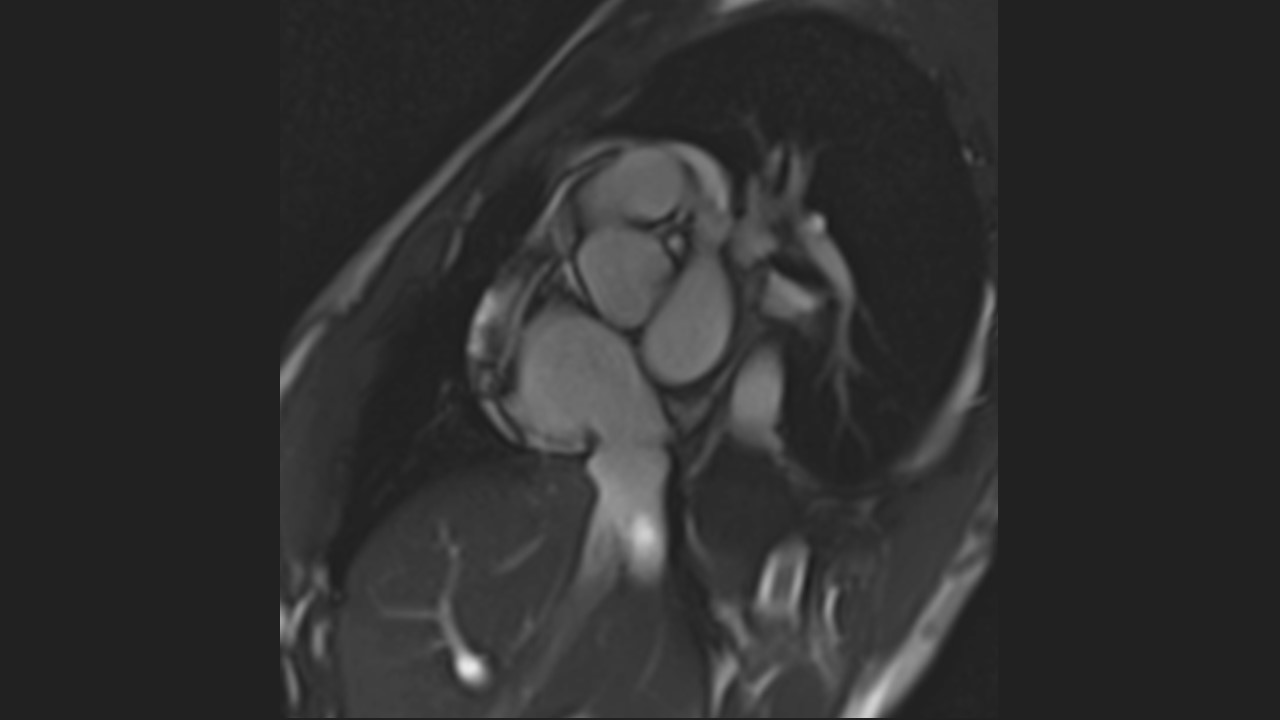

Short Axis Series